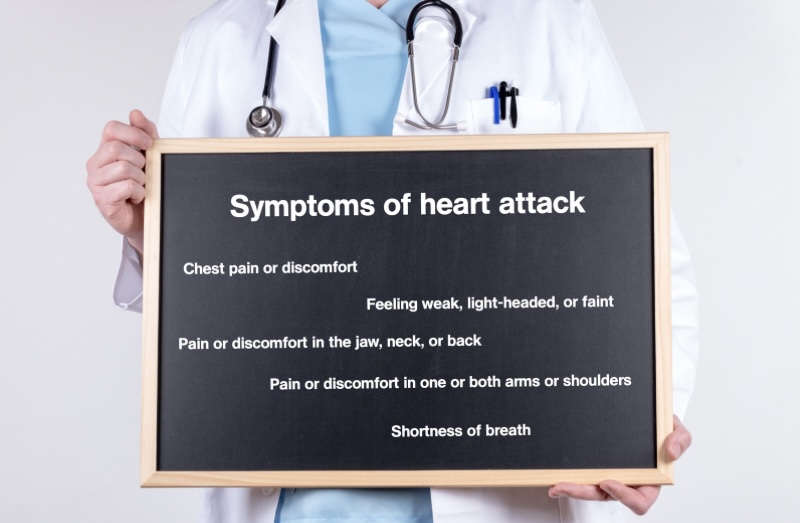

Young Age me Heart Attack ke Common Lakshan

Har insaan me symptoms thode alag ho sakte hain, lekin ye shuruaati signs common hain:

1. Seene me dabav ya jalan

Chest ke beech me pressure, heaviness ya tightness.

2. Left side me dard

Dard kandhe, baaye haath, gardan ya jabde tak ja sakta hai.

3. Saans lene me dikkat

Chhoti si activity me bhi saans phoolna.

Kab Emergency Samjhein?

Turant medical help lein agar:

- 5–10 minute se zyada chest pain ho

- Dard haath ya jabde tak jaye

- Saans lene me dikkat ho

- Achanak chakkar aaye